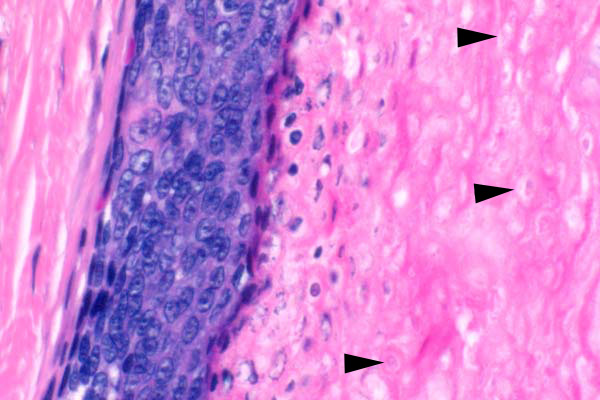

Abrupt keratinization is characterized by a sharp delineation between neoplastic cells and keratinaceous material. There are ghost cells in the keratin (arrowheads).